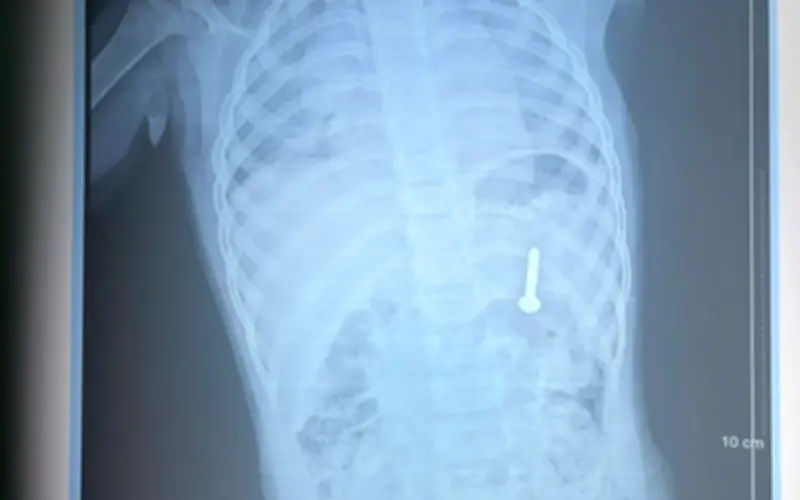

Sau khi thăm khám và chụp X-quang, các bác sĩ xác định dị vật nằm trong dạ dày của bệnh nhi. Nếu không được can thiệp ngay, dị vật có thể gây ra các biến chứng nghiêm trọng như thủng đường tiêu hóa, xuất huyết, và nhiều nguy cơ khác đe dọa tính mạng.

Chỉ trong vòng 30 phút, chiếc đinh vít đã được gắp ra thành công. Sau can thiệp, bệnh nhi được theo dõi sát sao tại Khoa Hồi sức cấp cứu, tình trạng sức khỏe ổn định và bé đã xuất viện ngay ngày hôm sau.